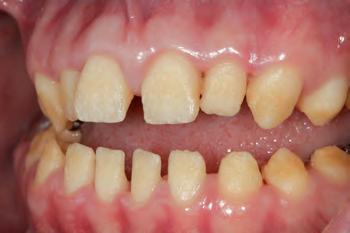

The patient was an 18-year-old male with a confirmed family history of Xlinked AI, who was otherwise in good health and non-smoking. Upon initial clinical presentation, a low-caries-risk, complete adult dentition from second molar to second molar was present, which was globally affected by pitted, hypoplastic and hypomineralised AI, dento-alveolar disproportion and an unusual generalised open occlusion, characterised by one occlusal contact at the right first molar region in the maximum intercuspation position (MIP). Historical paediatric management of the dentition involved placement of stainless steel crowns at the first permanent molar sites to protect the emerging dentition from post-eruptive breakdown and loss of occlusovertical dimension during the mixed dentition phase.6 On adult presentation, all but the UR6 stainless steel crown remained intact. Oral hygiene was poor, with evidence of plaque-induced chronic gingivitis (Figure 1). The patient reported experiencing severe, widespread hypersensitivity upon hot, cold, osmotic and masticatory stimuli, and feeling aesthetically self-conscious. The patient was seeking comprehensive fixed prosthodontic care and was well informed about the nature of such treatment, having witnessed his elder siblings undergo similar treatment.

1: The patient’s initial situation on clinical presentation to the tertiary care referral centre. The dentition is globally af fected by amelogenesis imperfecta, associated with dentoalveolar disproportion and an unusual presentation of open occlusion.

FIGURE 2: Initial treatment focussed on patient-driven improvements in oral hygiene, supplemented by professional mechanical plaque removal and ongoing fourmonthly supportive periodontal therapy. The patient demonstrated a sustained commitment to oral health behaviour change, as evidenced by the establishment of a robust, pale, pink and stable gingival architecture.